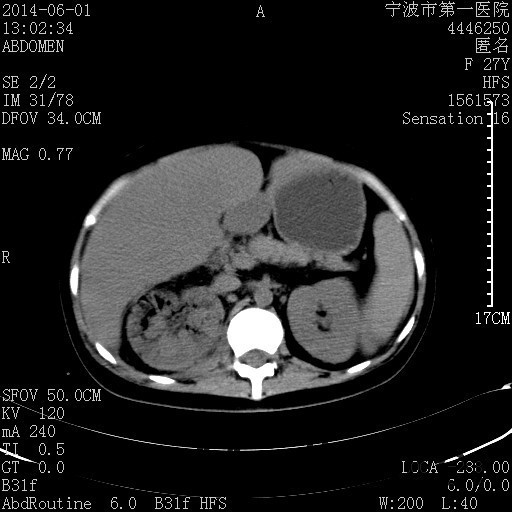

患者,女,27岁,因“右下腹疼痛伴呕吐2天”入院 患者无明显诱因出现右下腹疼痛伴呕吐、发热,体温最高39度,急诊CT示:右肾集气,考虑气性肾盂肾炎。

查体: 右肾区叩击痛,右下腹压痛,无反跳痛。 辅助检查: 空腹血糖9.7mmo/L,餐后血糖18mmol/L 血常规:白细胞 11.3*109/L, 中性百分比 77.4%, 血红蛋白 8g/L, 血小板 319*109/L 尿常规 WBC+++ 生化:白蛋白 37.5g/L,肝肾功能正常 泌尿系CT:右肾集气

诊断为“气性肾盂肾炎,感染性休克,糖尿病酮症酸中毒” 血、尿、脓液培养均示“克雷伯杆菌” 入院第2天行“右双J管置入术” 入院第3天、7天行“右肾穿刺造瘘术” 入院1月行“右肾切除术” 术后顺利康复出院。